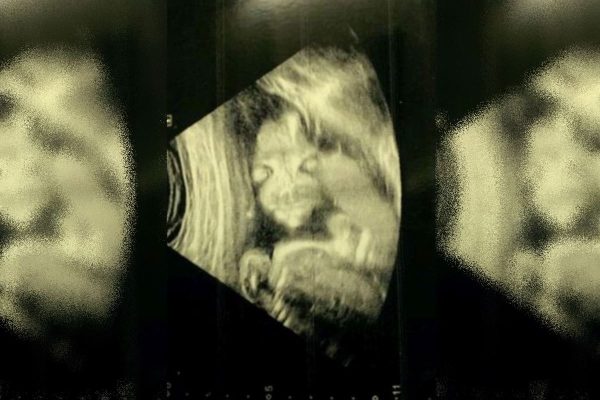

Mulher fica apavorada com ultrassom do próprio bebê: “Criança demônio”

Uma mulher grávida ficou assustada ao se deparar com resultados de um ultrassom realizado a fim de conhecer o próprio bebê. Conforme o jornal britânico The Mirror, Jade Boyland, de 28 anos, apelidou a criança não nascida de “bebê demônio”.

Animada para dar uma espiada no rostinho da filha pela primeira vez, Jade levou um baita susto. Isso porque o bebê foi flagrado de frente, e a imagem divertiu o médico. Apesar disso, ele garantiu que não havia nada de errado com a criança.

“Isso me assustou no começo, eu não sabia se era normal. Eu perguntei ‘o que é? Porque não parece certo’. Ele [o médico] apenas explicou que [o bebê] estava voltado para fora, então eu o chamei de ‘criança demônio’”, brincou a mãe.

“Eu levei um susto no começo, mas achei engraçado depois. Amigos e familiares riram quando viram o scan. Acho que muitos não viram um assim”, disse. Apesar do susto, a pequena Lydia Elwood nasceu bem e saudável logo depois.